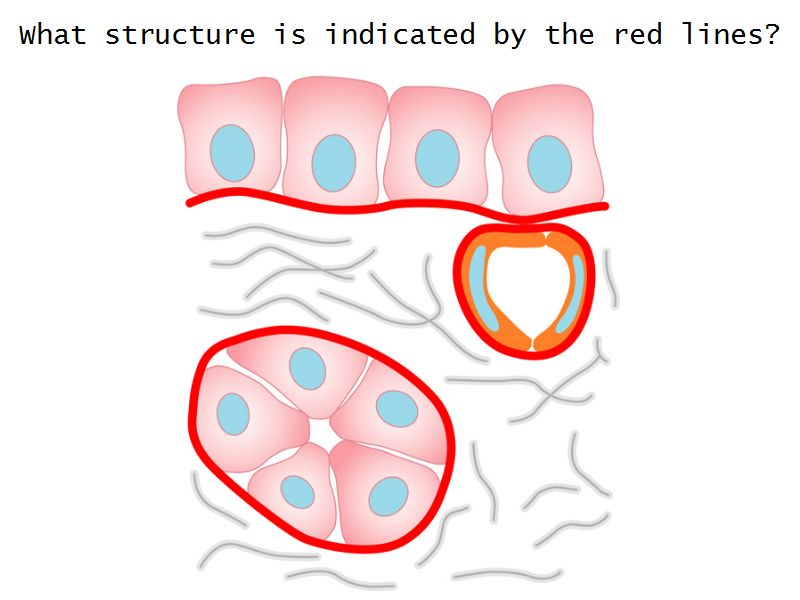

Epithelium layers

- Capillary endothelium

- Visceral layer of epithelium

- Podocytes

- Resting on glomerular basement membrane

- Capsular space

- Parietal layer of epithelium

- Simple squamous epithelium

Glomerular filtration barrier

- Three layers

- Fenestrated epithelium

- Exclude blood cells & platelets

- Glomerular basement membrane

- Main filtration barrier

- Thick

- Fused epithelial & endothelial BM

- Replenished by podocytes due to removal by mesangial cells

- Glomerular epithelium

- Through filtration slit